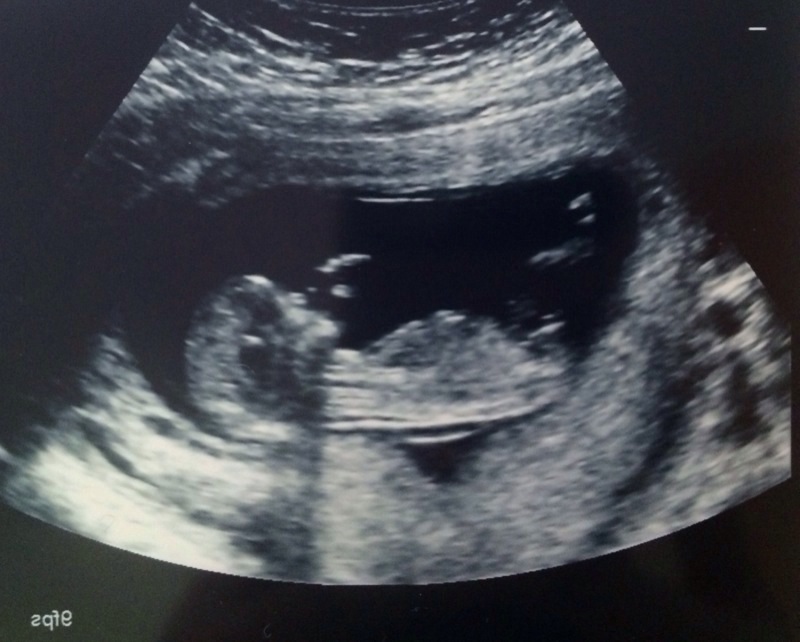

Hi! I'm new to these forums, and just learned about the "nub theory" (although still a bit confused about what to look for). This is my ultrasound from today, baby is 13 weeks. Any guesses for boy or girl? I already have three daughters, this is my last baby and I'd love to finally get a boy! Thanks for your help!!Attachment 25249

I'm going to say boy. This nub looks just like my DS2. I hope you get your boy!!